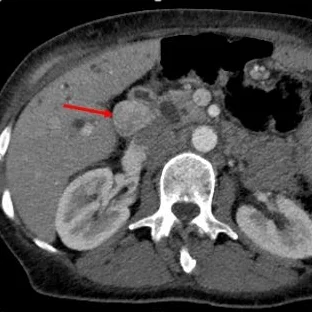

Conventional CT (axial plane): Mass in porta hepatis (red arrow).